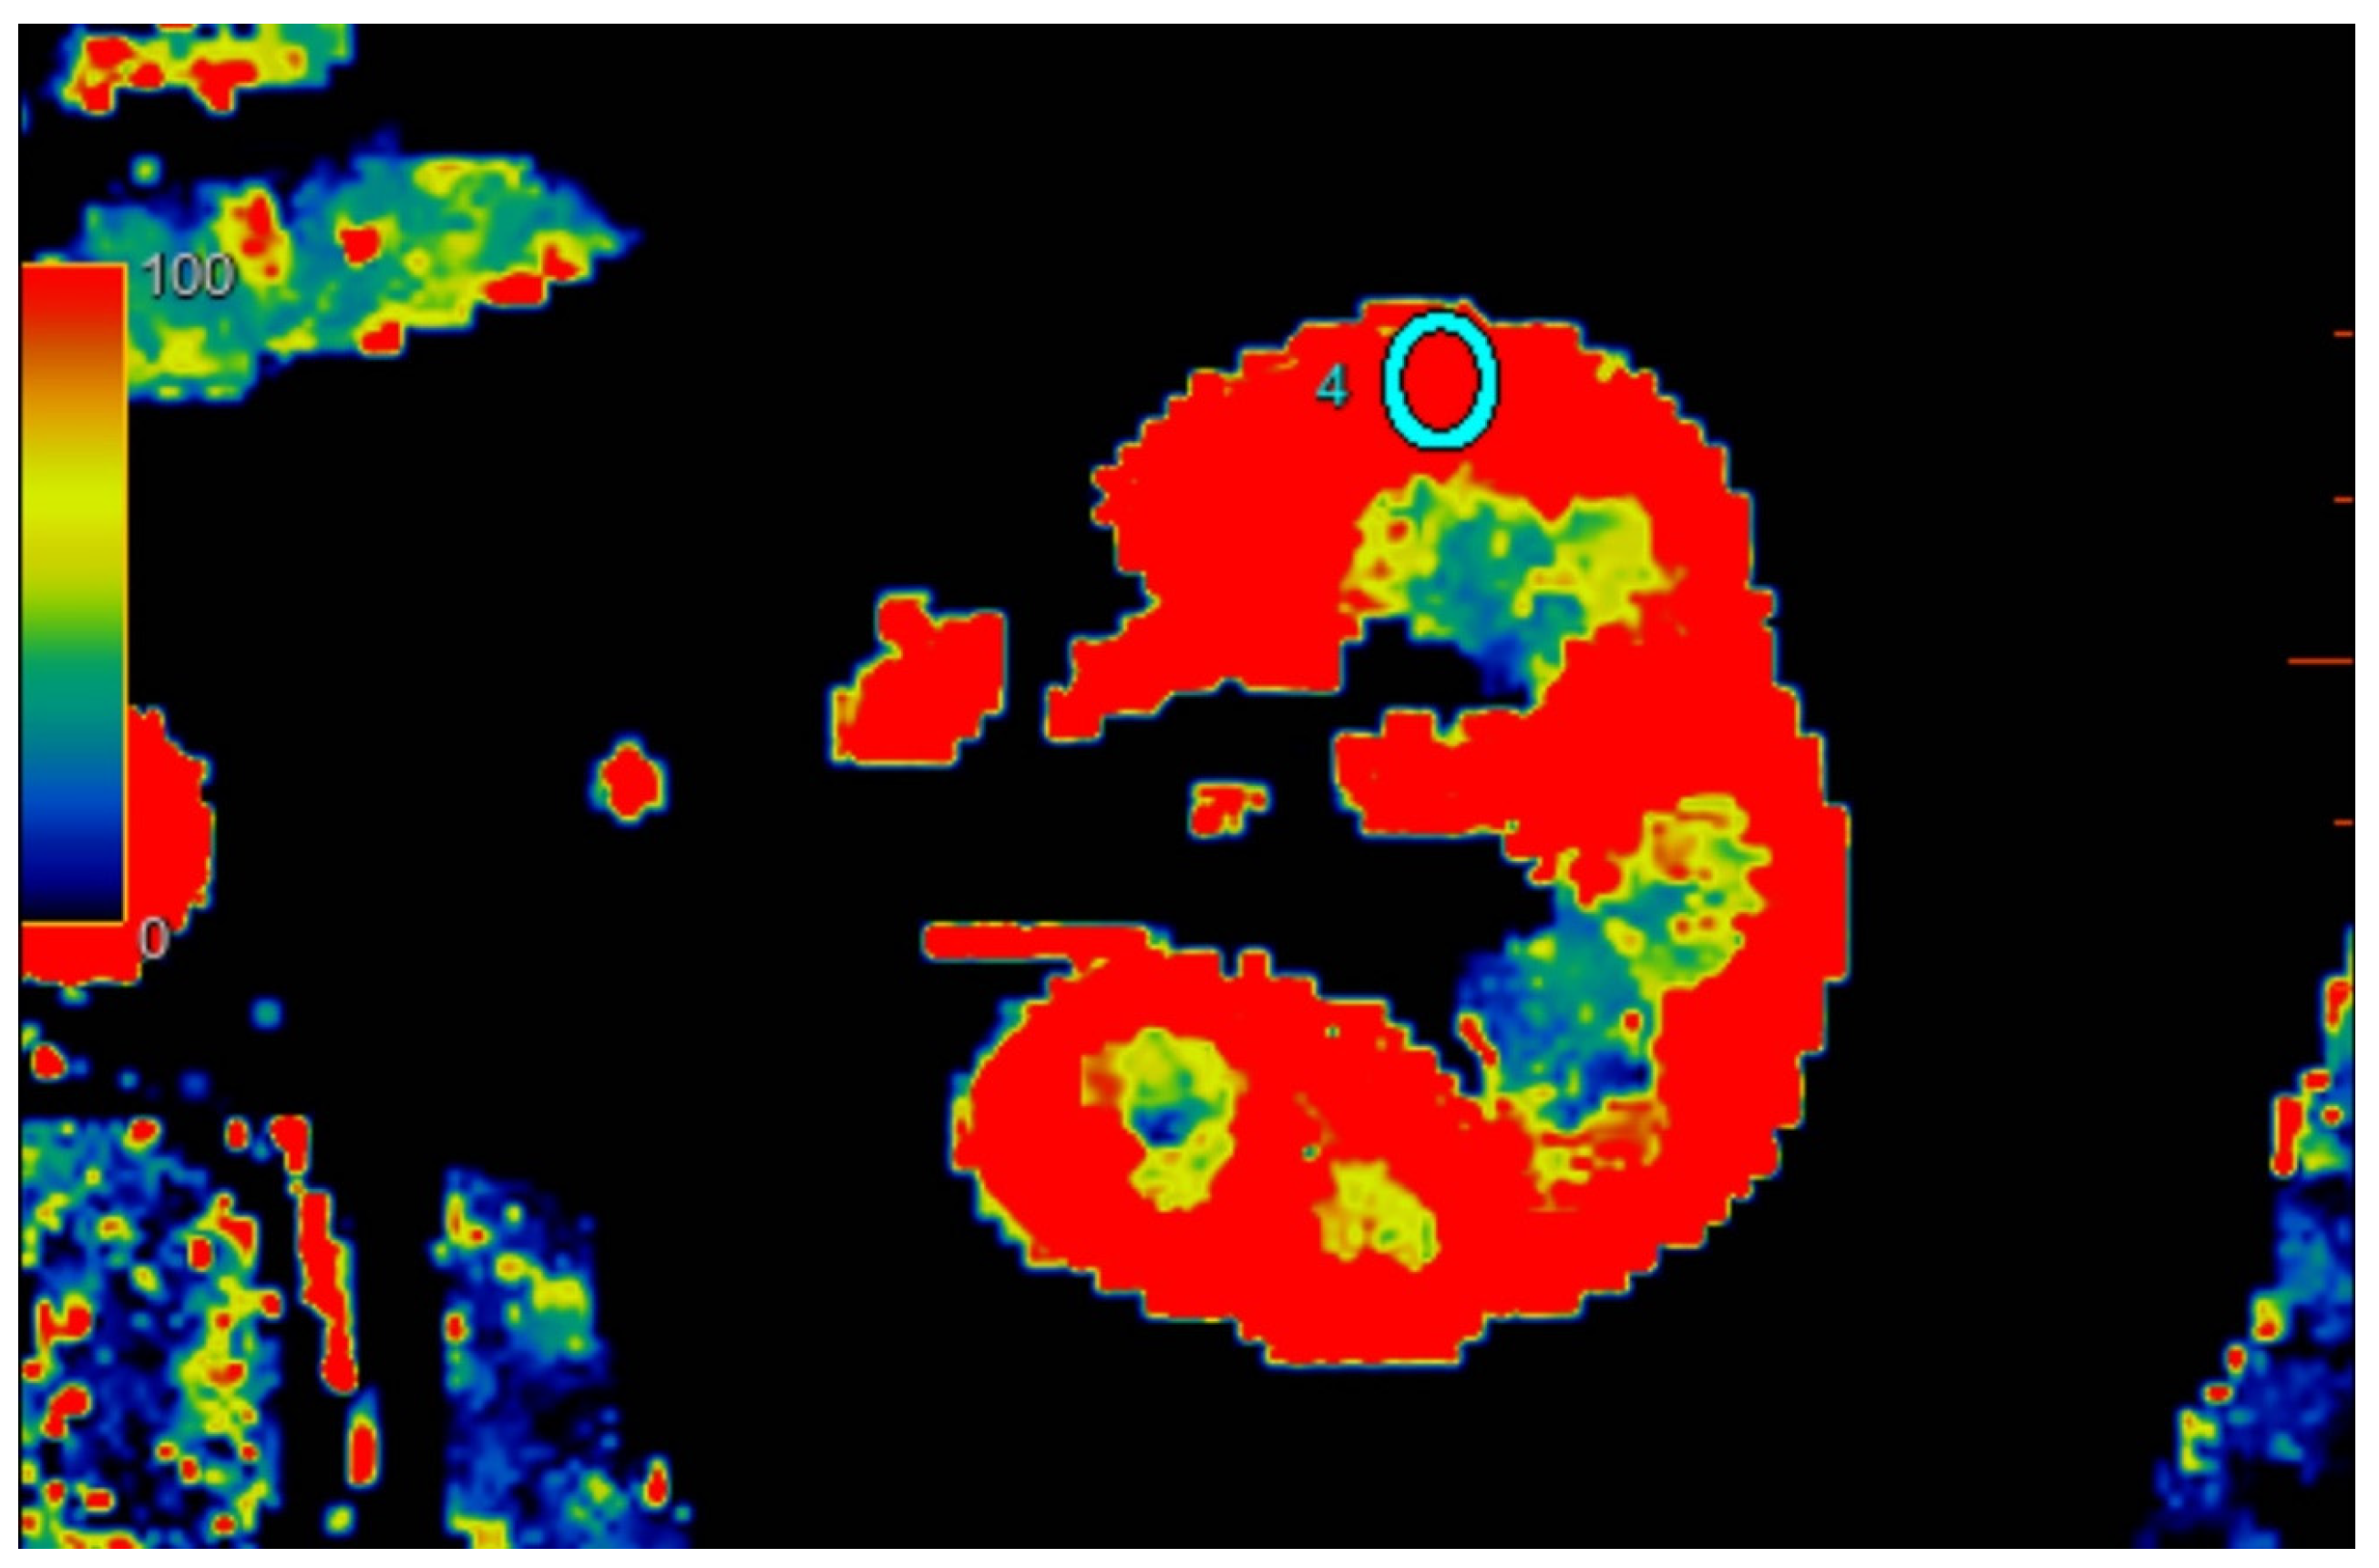

2.2.2. Quantitative Analysis of Perfusion